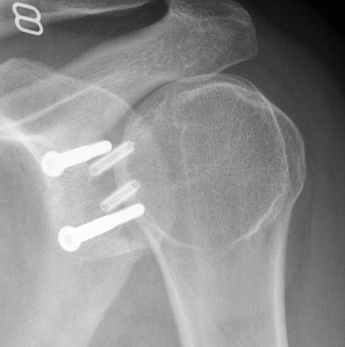

Case 1: Failed Latarjet

Case 2: Large glenoid defect